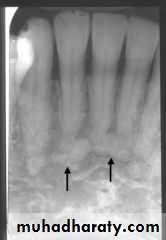

CT axial view : sequestra (arrows)

Radiographic examination: • Panoramic, intraoral periapical, and occlusal films.

CT scanning is good for detecting periosteal new bone formation and sequestra.